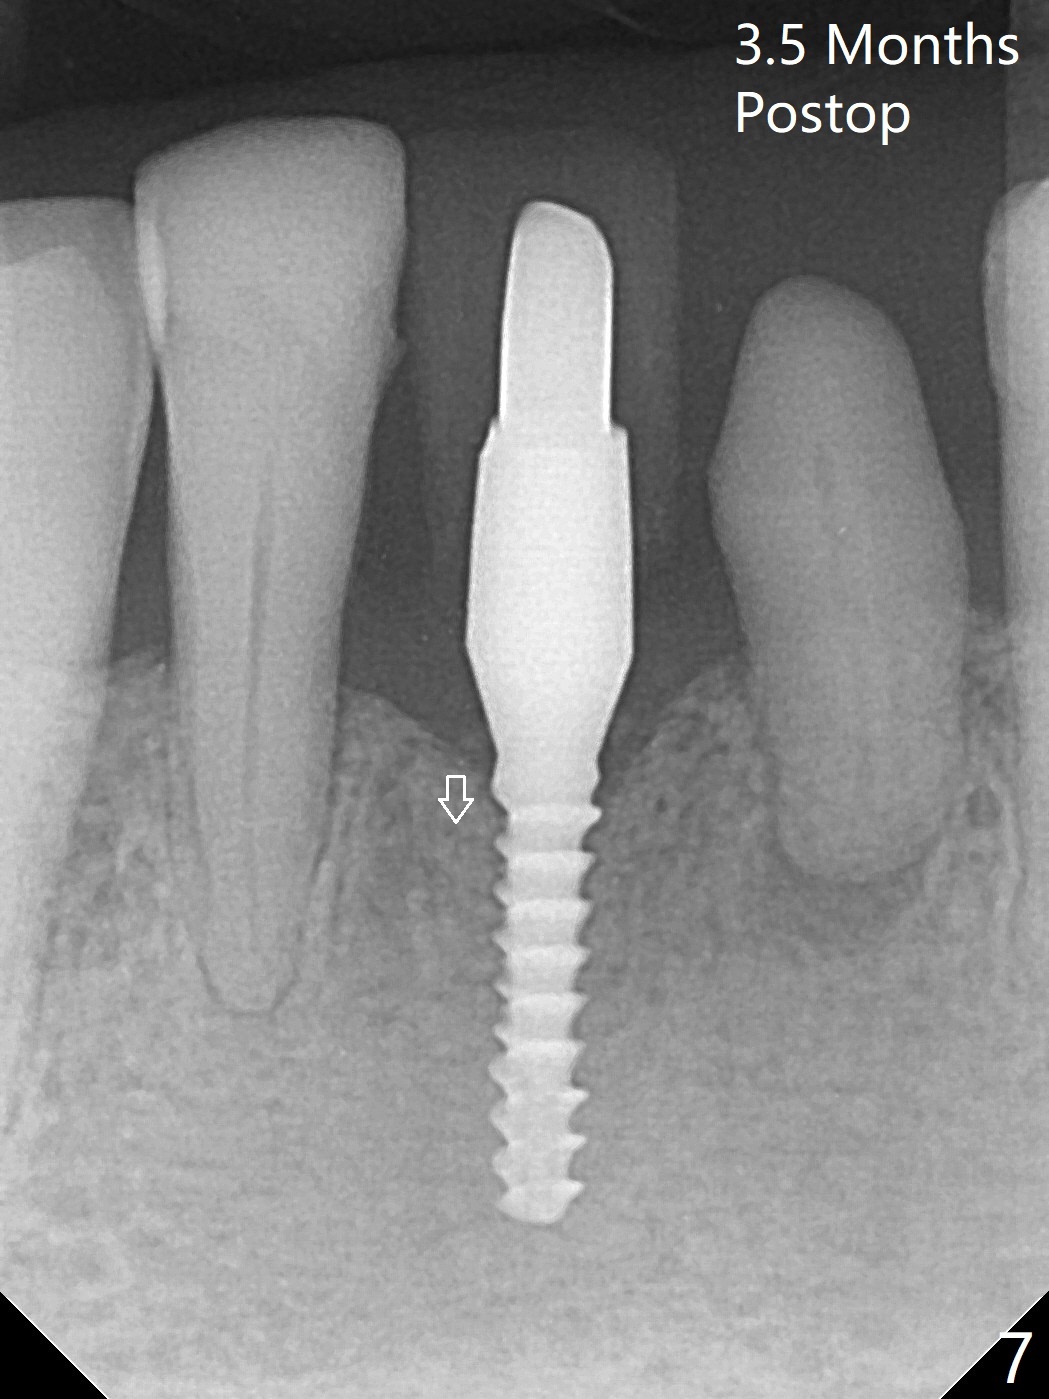

左下第一磨牙(#19)牙槽嵴狭窄,2.2毫米钻头完成导板钻洞后,舌侧骨板开始破裂(图一:<),打消牙槽嵴劈开术念头,放置2.5x8.5毫米一段式植体(图二(8.5毫米是最短植体)),好像离下齿槽神经管还有一定距离,适当植入深些(图四:箭头,15Ncm)。右下中切牙缺牙区牙槽嵴也十分狭窄(图四),最后不得不徒手植入2x8.5毫米植体(图五,六,25Ncm)。如果按设计植入2x12毫米植体,颊侧,或者舌侧骨板更容易穿孔。术后3.5月牙槽嵴下降(图七:箭头),可能术中那里压力太大,今后牙槽嵴钻洞要大。24号牙根尖阴影(图七),完成根管治疗(图八)。19牙位牙槽嵴吸收也严重(图九)。其实术后4个月19牙位牙槽嵴吸收并不严重(图十一)。